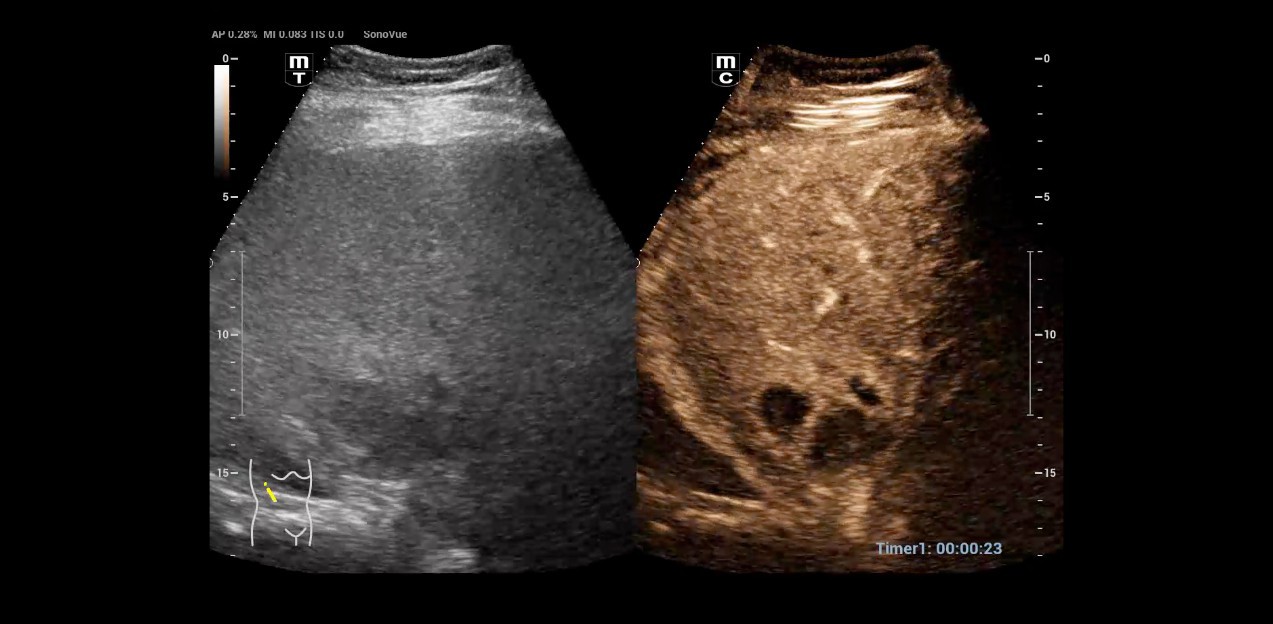

FÞr das Resona I9 hat sich Dr. Seibel aus verschiedenen GrÞnden entschieden. Zun?chst einmal, weil das High-End-Ger?t neben einer ausgezeichneten Bildqualit?t mit hoher Aufl?sung auch die M?glichkeiten zu fokussierten Untersuchungstechniken bietet, die ihm die Diagnosestellung erleichtern. So nutzt der Stationsleiter beispielsweise viel und gern den kontrastmittelverst?rkten Ultraschall (CEUS), um unklare Befunde abzukl?ren.